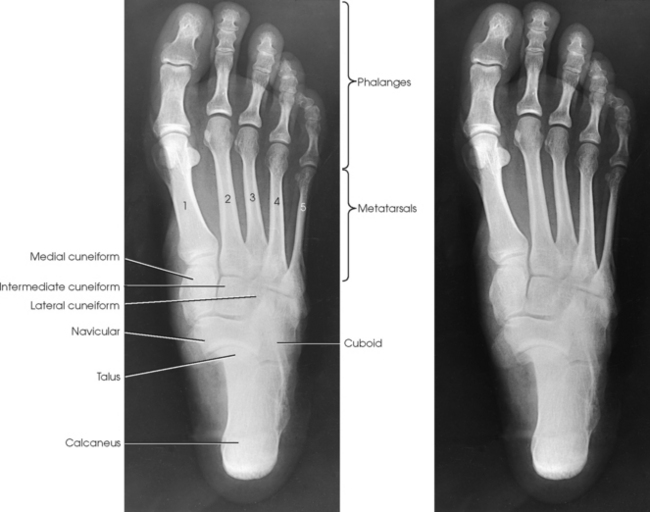

The foot consists of 26 bones (Figs. 6-1 and 6-2):

The bones of the foot are similar to the bones of the hand. Structural differences permit walking and support of the body’s weight. For descriptive purposes, the foot is sometimes divided into the forefoot, midfoot, and hindfoot. The forefoot includes the metatarsals and toes. The midfoot includes five tarsals—the cuneiforms, navicular, and cuboid bones. The hindfoot includes the talus and calcaneus. The bones of the foot are shaped and joined together to form a series of longitudinal and transverse arches. The longitudinal arch functions as a shock absorber to distribute the weight of the body in all directions, which permits smooth walking (see Fig. 6-2). The transverse arch runs from side to side and assists in supporting the longitudinal arch. The superior surface of the foot is termed the dorsum or dorsal surface, and the inferior, or posterior, aspect of the foot is termed the plantar surface.

Each foot has 14 phalanges—2 in the great toe and 3 in each of the other toes. The phalanges of the great toe are termed the distal and proximal phalanges. The phalanges of the other toes are termed the proximal, middle, and distal phalanges. Each phalanx is composed of a body and two expanded articular ends—the proximal base and the distal head.

The five metatarsals are numbered one to five beginning at the medial or great toe side of the foot. The metatarsals consist of a body and two articular ends. The expanded proximal end is called the base, and the small, rounded distal end is termed the head. The five heads form the “ball” of the foot. The first metatarsal is the shortest and thickest. The second metatarsal is the longest. The base of the fifth metatarsal contains a prominent tuberosity, which is a common site of fractures.

The proximal foot contains seven tarsals (see Fig. 6-1):

Beginning at the medial side of the foot, the cuneiforms are described as medial, intermediate, and lateral.

The cuboid bone lies on the lateral side of the foot between the calcaneus and the fourth and fifth metatarsals (see Fig. 6-1). The navicular bone lies on the medial side of the foot between the talus and the three cuneiforms. The cuneiforms lie at the central and medial aspect of the foot between the navicular bone and the first, second, and third metatarsals. The medial cuneiform is the largest of the three cuneiform bones, and the intermediate cuneiform is the smallest.